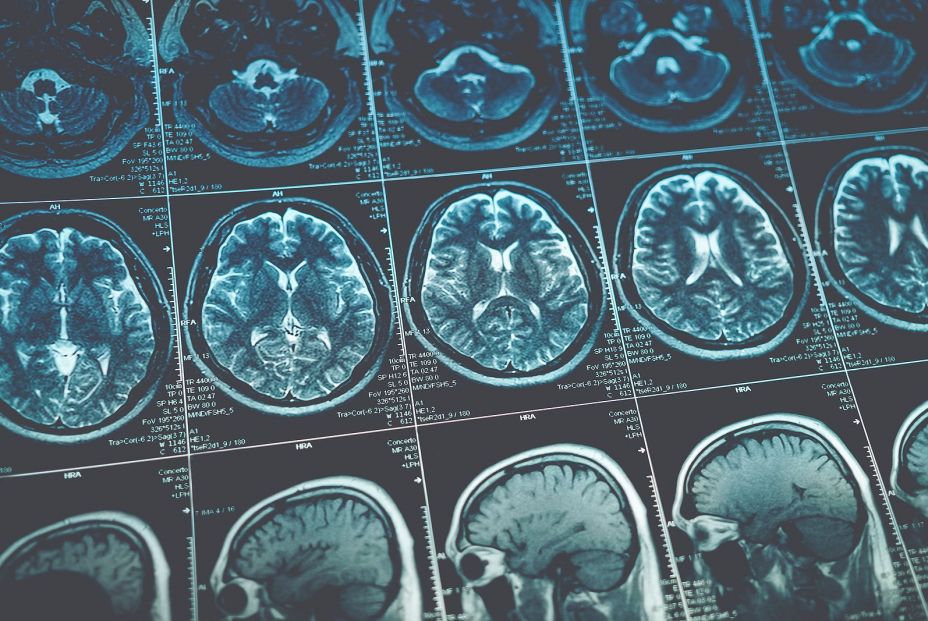

Basta con un poco de esfuerzo más para lograr grandes beneficios para la salud cerebral. El alzhéimer (EA) es una enfermedad neurodegenerativa que supone la primera causa de demencia a nivel mundial. Se estiman unos 40 millones de personas en el mundo afectadas de demencia atribuible a ella. En España, según datos de la Sociedad Española de Neurología (SEN), podrían existir unas 800.000 personas con esta patología.

Con la creciente popularidad de los dispositivos digitales portátiles, el recuento diario de pasos se ha convertido en una medida de actividad física fácilmente accesible y comprensible. Según un nuevo estudio, aumentar el número de pasos, aunque sea un poco, podría ayudar a ralentizar la progresión de la enfermedad de Alzheimer en personas con mayor riesgo. En un artículo publicado en Nature Medicine, investigadores del Mass General Brigham (Reino Unido) descubrieron que la actividad física se asociaba con una menor tasa de deterioro cognitivo en adultos mayores con niveles elevados de beta-amiloide, una proteína relacionada con el Alzheimer.

"El presente estudio abordó estas cuestiones utilizando una cohorte ampliada del Estudio del Envejecimiento Cerebral de Harvard (HABS) de personas mayores de la Universidad de Colorado (CU) con datos de actividad física medidos con podómetro, tomografía por emisión de positrones (TEP) longitudinal de Aβ y tau, y evaluaciones cognitivas anuales durante un máximo de 14 años. Examinamos si la actividad física se asocia con un deterioro cognitivo y funcional más lento a través de diferentes tasas de acumulación de Aβ y tau. Además, analizamos las relaciones dosis-respuesta con los niveles de actividad física para contribuir al desarrollo de futuros ensayos de prevención de la enfermedad de Alzheimer y políticas de salud pública", documentan los investigadores en su trabajo.

Los investigadores analizaron datos de 296 participantes de entre 50 y 90 años del Estudio del Envejecimiento Cerebral de Harvard, quienes no presentaban deterioro cognitivo al inicio del estudio. Como hemos comentado anteriormente, utilizaron tomografías por emisión de positrones (PET) cerebrales para medir los niveles basales de beta-amiloide en placas y de tau en ovillos neurofibrilares, y evaluaron la actividad física de los participantes mediante podómetros de cintura. Los participantes se sometieron a evaluaciones cognitivas anuales de seguimiento durante un periodo de entre dos y catorce años (promedio = 9,3 años), y un subgrupo se sometió a (PET) repetidas para monitorizar los cambios en la proteína tau.